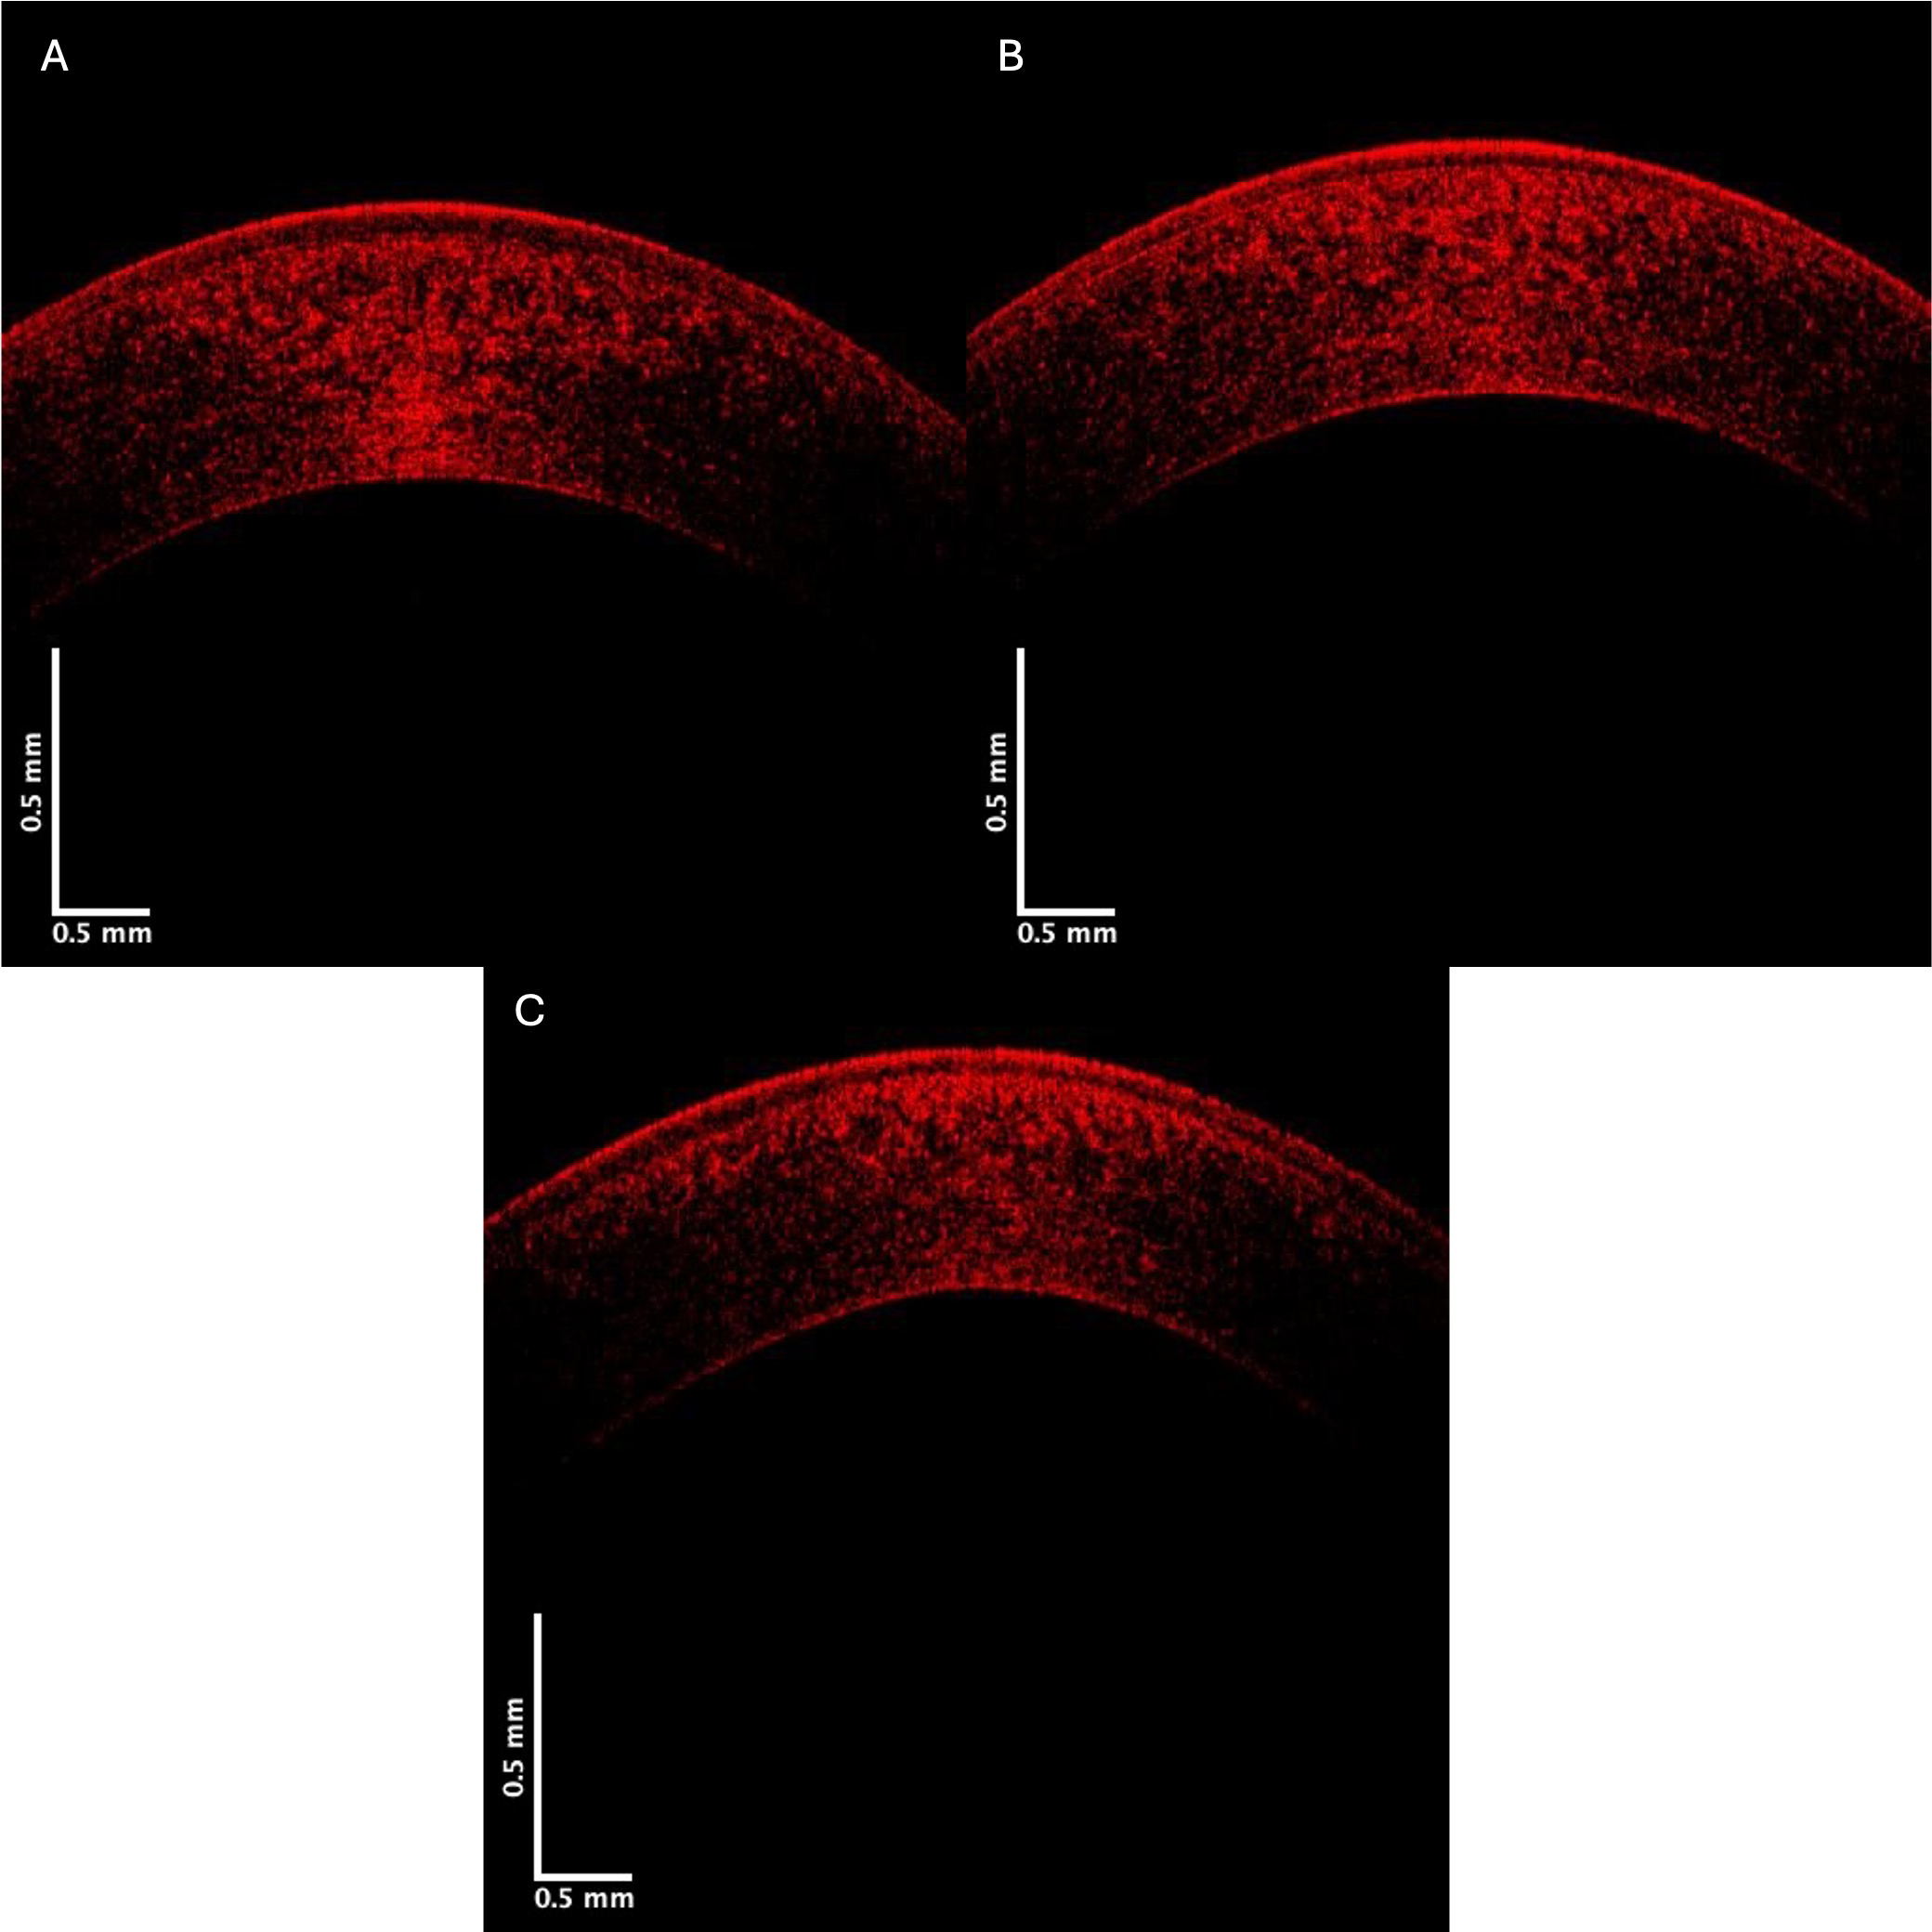

The data in Table 6 appear to show a more rapid decrease in the pixel intensity versus depth plot for the blue channel in the central corneas for KC Stages III and IV (C) than in KC Stages I and II, and compared to the control. However, the pixel intensity at a depth of 0.25 mm for the blue and red subchannels was not significantly different from the controls. Figs. 7,8 present red channel OCT images and pixel intensity versus depth plots, respectively. Table 7 shows the initial slopes for the control versus Stage I and II and Stage III and IV KC corneas. The decrease in the red channel slope is statistically higher for Stage I and II and Stage III and IV KC corneas than for the control.

Fig. 7. Typical central corneal red channel cross-sectional images of control (A), Stage II (B), and Stage IV (C) KC corneas. Note the apparent loss in pixel intensity for the lower corneal lamellae in the Stage IV cornea.

Fig. 8. Typical plots of central cornea red channel pixel intensity versus depth for control (A), Stage II (B), and Stage IV (C) KC corneas—based on Fig. 7. Note the lower pixel intensity of the posterior Stage III and IV KC corneas suggests that the keratocytes and collagen contents in the posterior corneas are progressively affected alongside the increasing disease stages. Arrows indicate the points between which the slope was calculated.

The results reported in this study suggest that the pixel intensity of KC corneas appears to reduce more rapidly with depth compared to controls. This reduction could be explained by decreased cell density or collagen content in KC corneas compared to controls. Moreover, the relative changes in reflection from cellular (green), collagen (blue), and both cellular and collagen contents (red) in the cornea can be evaluated by separating the OCT images into low (green), medium (blue), and high subchannel pixel intensity versus depth plots. This relationship between low pixel intensity (green channel) and cellular content and medium pixel intensity (blue channel) and collagen content was previously established for skin [12]. The rapid decrease in the slope in the green channel suggests a reduced cellular content in the anterior cornea in KC, especially in Stage I and II corneas. Pixel intensity differences in the green channel at a depth of 0.25 mm suggest that the keratocyte content decreases in the posterior corneas in Stages III and IV. These results in the green channel OCT images indicated that the epithelial cell content in the anterior cornea is the first change observed in the early KC stages. Meanwhile, the green channel in the Stage IV posterior cornea almost disappears (Figs. 2,3), suggesting a decrease in the keratocyte content in the posterior cornea occurs in later KC stages. The reduced collagen content observed in the blue channel (Figs. 5,6) follows the loss of epithelial cells and is coincidental following the loss of keratocytes in the posterior cornea.

The red channel appears to reflect both the cellular and collagen content in the cornea [12]. As seen in Figs. 7,8, and Table 5, the reflections of the cellular and collagen contents appear to reduce with increased depth. These preliminary results suggest that corneal epithelial and keratocyte changes are seen both in the anterior and posterior cornea during the pathogenesis of KC, and may precede collagen changes in the posterior cornea. Furthermore, these results suggest that the early phases of KC can be observed based on changes in the green subchannel OCT images after the construction of pixel intensity versus depth plots. Reviewing the green, blue, and red subchannel OCT images may represent a screening tool for detecting early changes in the corneal structure in KC and other corneal diseases; however, additional studies are needed to confirm these data.